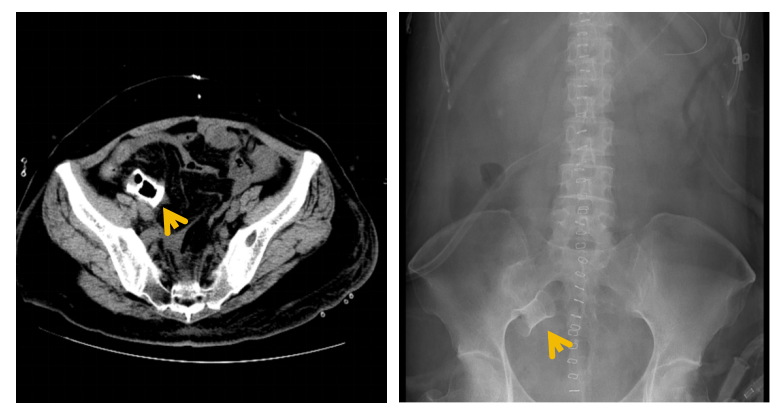

图3:术后盆腔CT及腹部平片可见完整小肠支架影子(箭头)